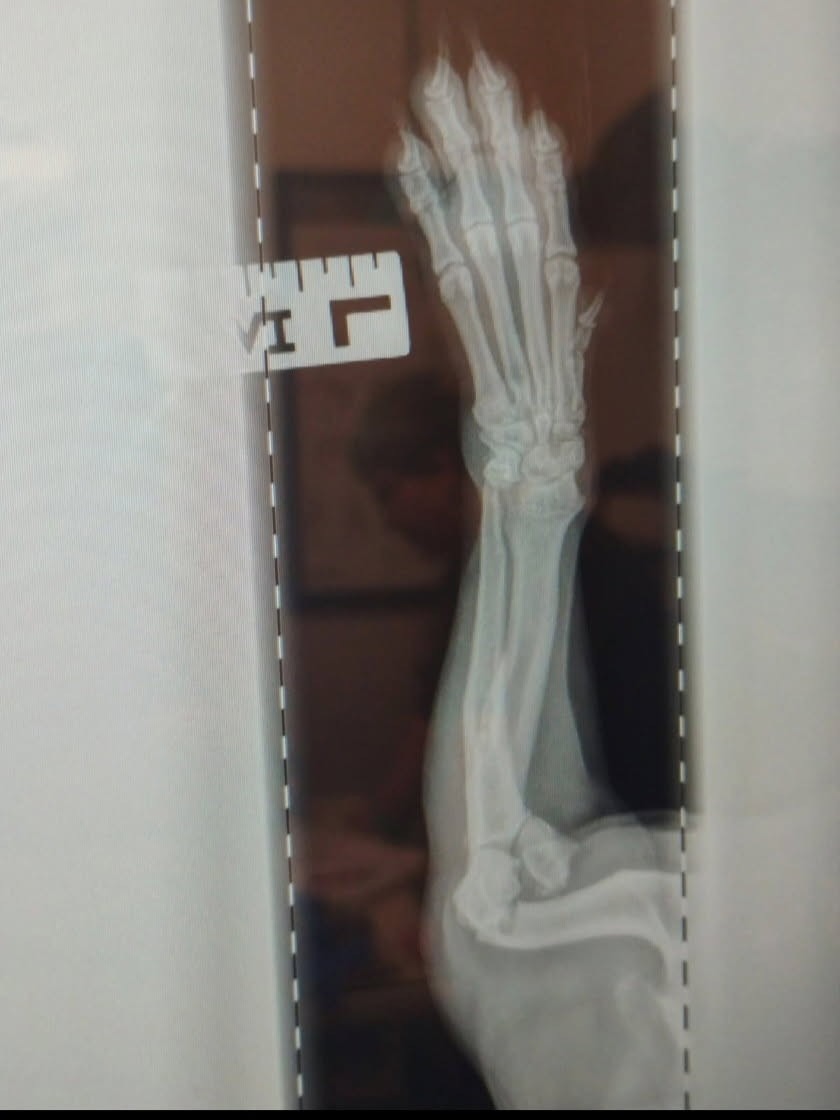

After several tests and X-rays, the ER vets gave me devastating news: Dukes had fractured his humerus and shattered his elbow in three places. He needs major orthopedic surgery to recover. Without it, his quality of life will be deeply affected.